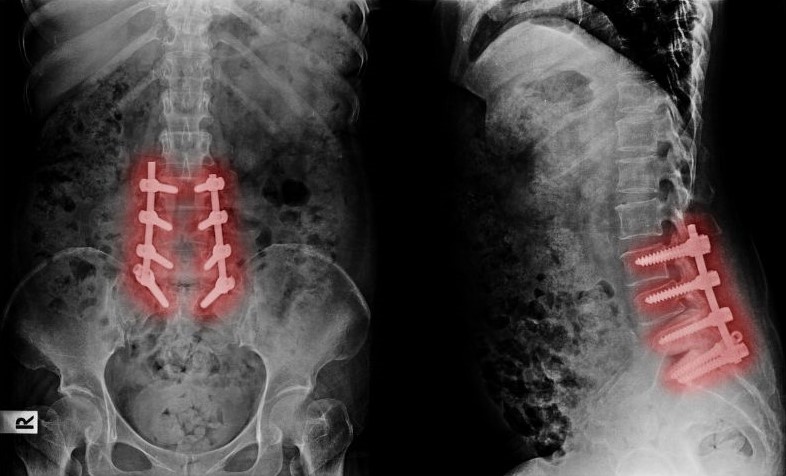

4. Điều trị phẫu thuật

Các bác sĩ sẽ chỉ định phẫu thuật khi người bệnh có những triệu chứng đau nặng, kéo dài mà khi điều trị nội khoa không hiệu quả. Khi tình trạng thoái hóa ngày càng nặng, chèn ép hệ thống dây thần kinh dẫn đến tê liệt nghiệm trọng, can thiệp phẫu thuật là bắt buộc.

Phẫu thuật nội soi cột sống là phương pháp điều trị được áp dụng phổ biến hiện nay. Đây là hình thức phẫu thuật cột sống tiên tiến, ít xâm lấn, có thể giúp người bệnh rút ngắn thời phục hồi, giảm đau và dễ chăm sóc hơn so với những phương pháp phẫu thuật cột sống truyền thống. Ngoài ra, phương pháp này còn giúp người bệnh duy trì phạm vi di chuyển bình thường của cột sống sau phẫu thuật.